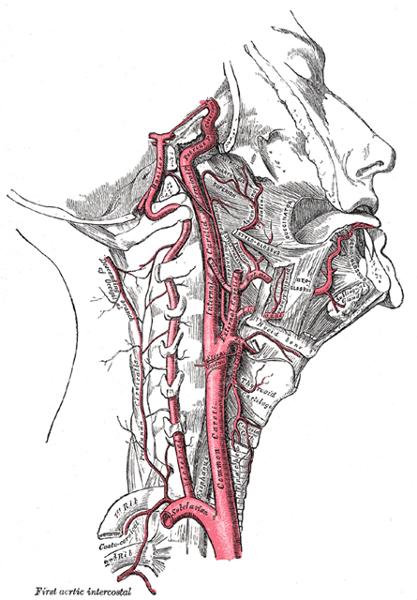

Name the branches of the aortic arch

- Right Innominate/Brachiocephalic

- Right CCA

- Right Subclavian artery

- Left CCA

- Left Subclavian artery